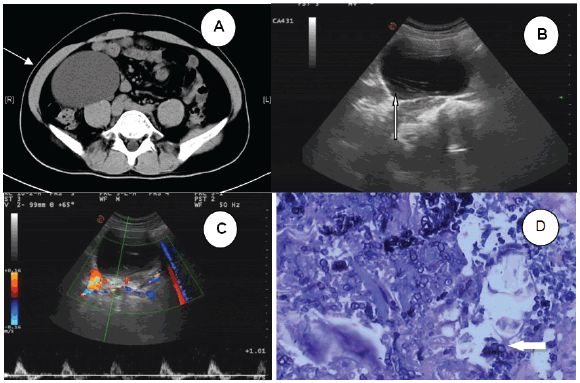

图1 (A)腹部CT扫描显示右腹膜后囊肿肿块(箭头) (B)超声检查显示囊肿内部低回声区周围边缘模糊的带状高回声病灶(箭头) (C)CDFI未见明显血流信号 (D)术后病理示钙质微粒和蠕虫组织(箭头)

2016年5月,中南大学湘雅医学院附属海口医院收治了一位患者。患者男性,42岁,工作稳定(小学教师),未去过海外。3月前,体检偶然发现右上腹部囊性肿块。腹部CT扫描显示右腹膜后囊肿肿块,信号强度低,边界清晰,大小约为9.4×7.6×9.2cm,增强CT未见异常。肿块紧靠右肾下部,且部分升结肠向左移位(图1A)。患者无发烧、腹痛等症状,其它体检指标均正常。研究人员初步影像学诊断为淋巴囊肿,告诉患者有必要进一步检查和治疗,但患者还是拒绝并出院回家。

患者于2016年8月再次来院就诊,希望手术切除肿块。入院时复查超声示右上腹部囊性肿块,肿块内可见带状高回声病灶,周围低回声区边缘模糊。彩色多普勒血流显像(CDFI)显示内侧未见明显血流(图1B C)。这次,患者也无发烧、腹痛等症状,其它体检指标均正常。然而,接诊医师未发现两次检查结果差异,且缺乏怀疑,故给出了同样的诊断。

术后病理报告为sparganosis,其中部分囊壁为输尿管组织,免疫组化显示SMA(+),S-100(-),Vim(+),HMB45,CD68(-)(图1D)。术后实验室检查:白细胞计数16.16×109/L,中性粒细胞比例增加(14.8%),C反应蛋白23.2mg/dl。在给予吡喹酮两个疗程后,患者所有实验室指标均在正常范围,出院时伤口愈合良好。1月后,患者无任何不适,血常规、尿常规、肝功、肾功均正常。随后,研究人员通过膀胱镜取出双J管。Sparganum(裂头蚴)血清抗体滴度为阴性,盆腔、腹部超声中均未发现异常。术后患者每3月复查1次,随访近1年未发现异常。